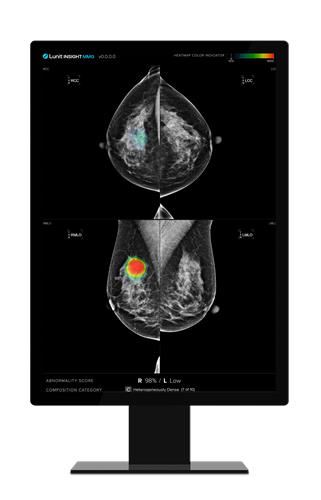

루닛 인사이트 MMG는 유방 촬영 영상을 분석해 유방암 등 의심 부위를 검출하는 설루션이다. 환자가 유방촬영술을 받으면 유방 사진이 의료진 측에 전달되는데, 루닛 인사이트 MMG는 해당 사진에 종양이나 석회 등 의심 부위를 동그랗게 표시해준다. 유방 치밀도도 분석한다.

이날 기자가 직접 유방촬영술을 받은 뒤 루닛 인사이트 MMG로 분석된 사진을 보자 유방암 발생 가능성, 유방 치밀도 수준 등이 일반 환자도 알기 쉽게 직관적으로 표시된 것을 확인할 수 있었다.

루닛 인사이트 MMG [루닛 제공. 재판매 및 DB 금지]